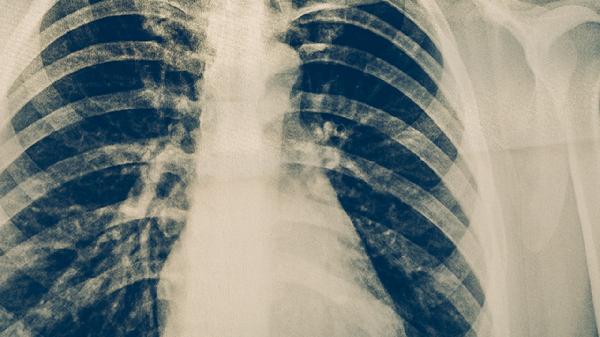

肺結(jié)核主要表現(xiàn)為咳嗽、咳痰、咯血、胸痛、發(fā)熱、盜汗、乏力等癥狀,診斷方法主要有痰涂片檢查、痰培養(yǎng)檢查、胸部X線檢查、結(jié)核菌素試驗、分子生物學檢測等。肺結(jié)核是由結(jié)核分枝桿菌引起的慢性傳染病,主要通過呼吸道傳播,建議患者及時就醫(yī),積極配合醫(yī)生治療。

肺結(jié)核患者應注意保持室內(nèi)空氣流通,避免隨地吐痰,咳嗽、打噴嚏時遮掩口鼻。飲食上應保證足夠熱量和優(yōu)質(zhì)蛋白攝入,多吃雞蛋、牛奶、瘦肉、新鮮蔬菜水果等。適當進行散步等輕度運動,但避免過度勞累。嚴格遵醫(yī)囑完成全程抗結(jié)核治療,不可自行停藥,定期復查胸部影像學和痰菌檢查。密切接觸者應進行結(jié)核病篩查,兒童應及時接種卡介苗。